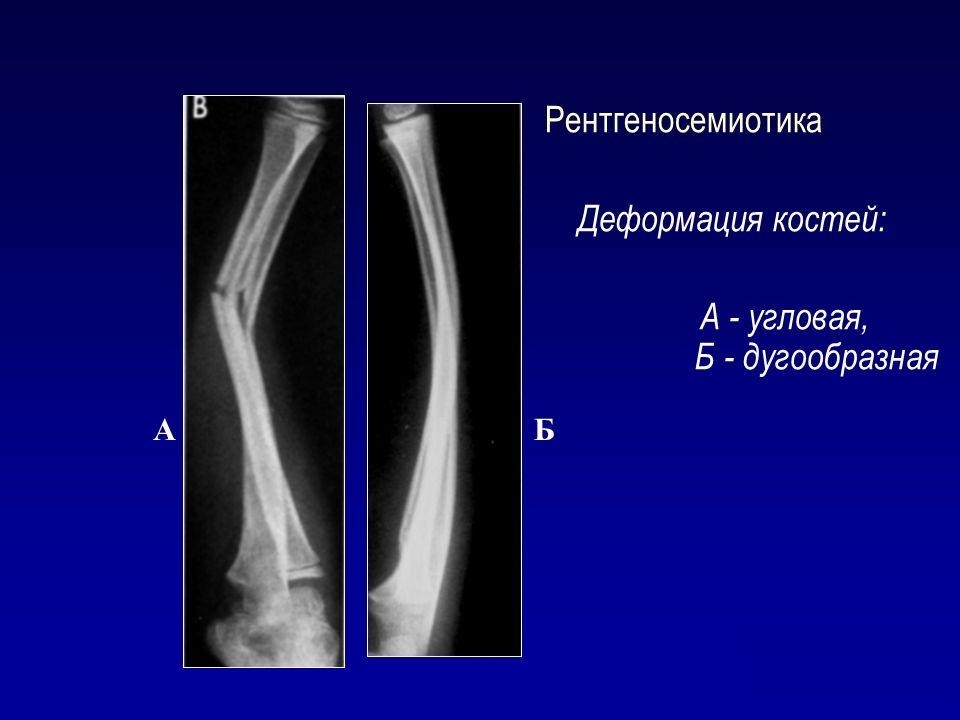

Угловая. При этой методике костные ткани вырезаются под определенным углом с обеих сторон, что позволяет установить их в нужное положение.